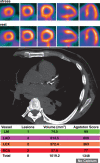

Positron emission tomography (PET) is increasingly being applied in the evaluation of myocardial perfusion. Cardiac PET can be performed with an increasing variety of cyclotron- and generator-produced radiotracers. Compared with single photon emission computed tomography, PET offers lower radiation exposure, fewer artifacts, improved spatial resolution, and, most important, improved diagnostic performance. With its capacity to quantify rest-peak stress left ventricular systolic function as well as coronary flow reserve, PET is superior to other methods for the detection of multivessel coronary artery disease and, potentially, for risk stratification. Coronary artery calcium scoring may be included for further risk stratification in patients with normal perfusion imaging findings. Furthermore, PET allows quantification of absolute myocardial perfusion, which also carries substantial prognostic value. Hybrid PET-computed tomography scanners allow functional evaluation of myocardial perfusion combined with anatomic characterization of the epicardial coronary arteries, thereby offering great potential for both diagnosis and management. Additional studies to further validate the prognostic value and cost effectiveness of PET are warranted.